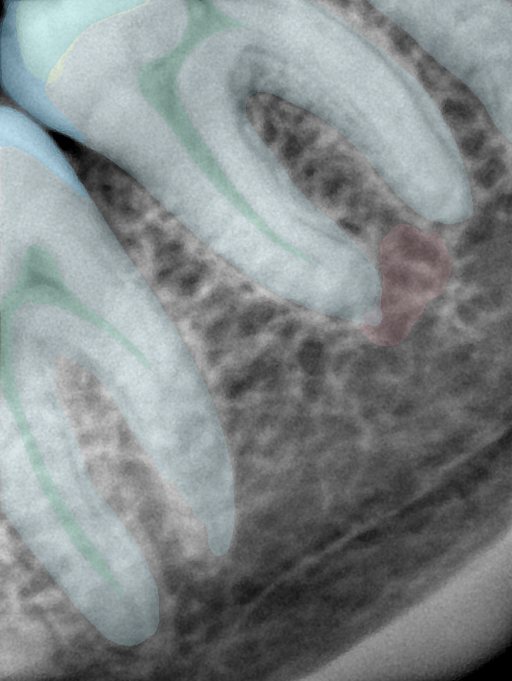

CR/DR 牙齿分割阶段记录

当前进展

- 完成了 CR/DR 牙齿相关分割训练

- 当前结果已经达到阶段预期,但仍有细节问题需要继续处理

相关测试

遇到的问题

- 训练过程中出现过 mask 下移问题

- 部分结果会出现 box 填充异常

- mask 边缘仍然有比较明显的锯齿感

参考

第二版算法问题测试

| 第一版 | 第二版 | 是否解决 | |

|---|---|---|---|

![]() | ![]() ![]() 边角识别有问题 龋齿识别不全 牙髓识别不全 | ![]() | 解决 |

![]() | ![]() 边角识别有问题 识别信息有误 自查(牙冠识别不全) | ![]() | 解决 |

![]() | ![]() ![]() 边角识别有误 大范围填充识别遗漏 | ![]() | 解决 |

![]() | ![]() 识别信息不全 | ![]() | 解决 |

![]() | ![]() ![]() 边角问题 牙胶识别不全 牙冠识别不全 | ![]() | 解决 |

![]() 换图片 | ![]() | ![]() 牙冠部分稍微白了一些就识别成小范围修补,部分判断异常 | 部分解决,修复类略敏感,牙冠部分稍微白了一些就识别成小范围修补,部分判断异常。 |

![]() | ![]() ![]() 牙冠识别不全 牙髓不全 根尖炎龋齿识别有误 | ![]() | 解决 |

![]() | ![]() | ![]() | 解决 |

![]() 换图片 | ![]() | ![]() | 解决 |

![]() | ![]() 牙冠识别有误 | ![]() | 解决 |

![]() 换图片 | ![]() ![]() 边角识别有误 | ![]() 修复类敏感 | 部分解决,图像过白,导致修复类判断异常。 |

![]() 换图片 | ![]() 牙冠识别不全 | ![]() 修复类敏感 | 部分解决,图像过白,导致修复类判断异常 |

结论:修复类出现了不鲁棒的情况,后续需要加入轮廓的扩充数据进行增强。